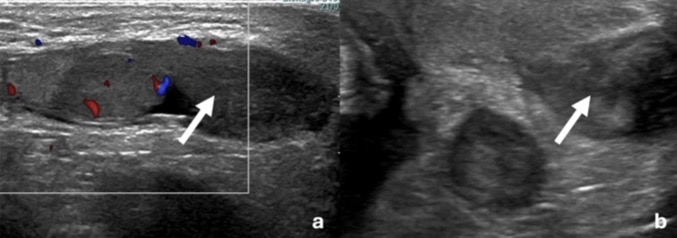

A J4: Hématome (flèche)